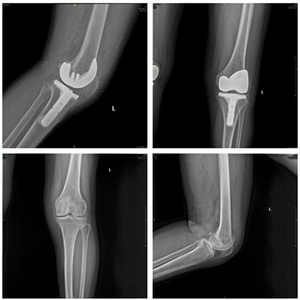

图说:上海第九人民医院团队为女性患者完成了全膝关节置换术 采访对象供图(下同)

李慧武介绍,术中“鸿鹄”机器人完美执行了医生的术前规划,高水准的完成了多项手术辅助操作。“鸿鹄”的自动定位截骨,避免了传统手术中采用髓内定位工具可能会对患者髓腔造成一定损伤等问题,很大程度减少了软组织和骨组织的损伤,患者出血少、创伤小,术后膝关节功能的康复会更快,感受会更优。同时,该手术机器人配合独有的内轴型膝关节假体,极大降低了因常规手术技术问题造成关节松动、力线不准、关节脱位等情况的发生率。患者术后X光检查报告显示,机器人辅助截骨能够实现精准力线恢复,患者预后效果良好,证明了该手术机器人相对传统手术具有独特的临床优势。